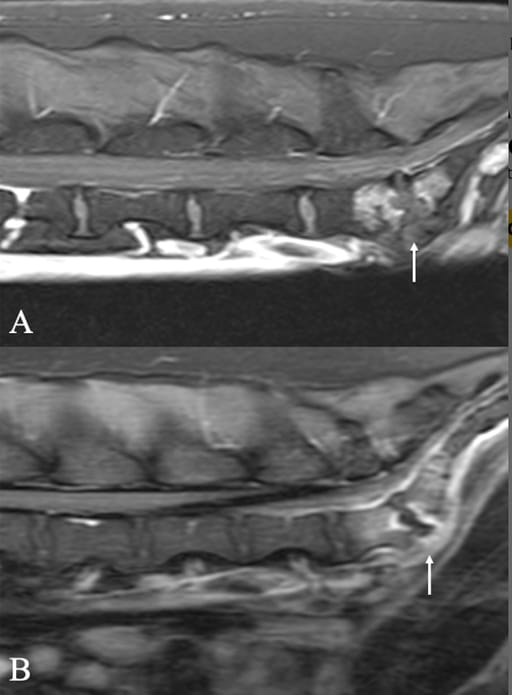

Sagittal post-intravenous contrast MRI images showing central lytic lesions in dogs with lumbosacral discospondylitis (arrows). (A) Brucella case. T1-weighted Dixon (water only, fat suppressed) sequence. (B) Control dog. T1-weighted FLAIR sequence.